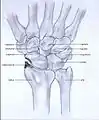

Post-traumatic osteoarthritis can be classified into four stages.[1][6] These stages are similar between SLAC and SNAC wrists. Each stage has a different treatment.

- Stage III: the osteoarthritis is localized in the entire radioscaphoid joint with involvement of the capitolunate joint.

Stage III